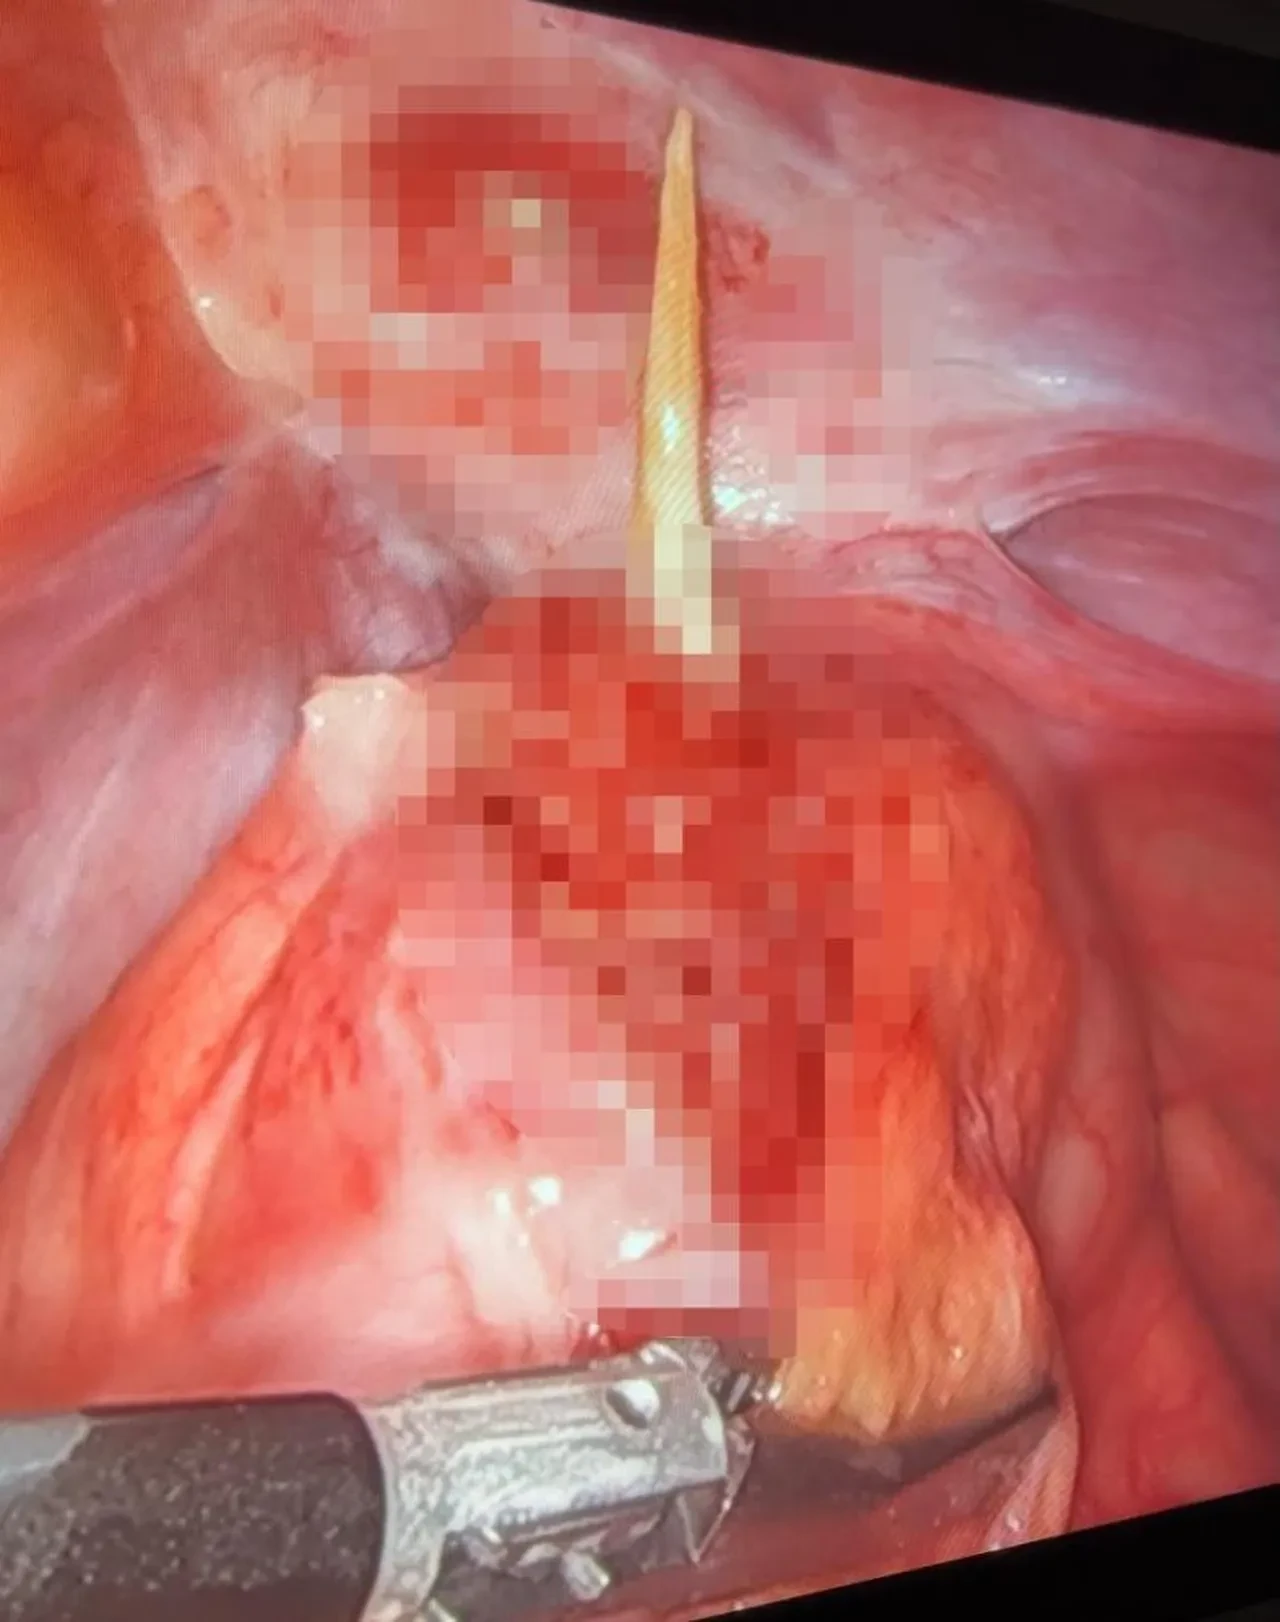

Tomografi sonuçlarının normal olduğu hastada, Radyoloji Uzmanı Dr. Zeynep Çetiner tarafından gerçekleştirilen ultrasonografi sırasında bağırsak bölgesinde şüpheli bir görüntü tespit edildi. Bu bulgunun ardından hasta hemen ameliyata alındı. Uzmanlar Opr. Dr. Aytaç Taşcı ve Opr. Dr. Sema Tural Bozoğlu tarafından gerçekleştirilen laparoskopik (kapalı) cerrahi işlemle, hastanın kalın bağırsağına saplanmış halde bulunan kürdan yalnızca üç küçük kesi ile çıkarıldı.

Sinop Atatürk Devlet Hastanesi’nden yapılan açıklamada şu ifadelere yer verildi. "Türkiye’de daha önce biri çocuk olmak üzere toplamda 3 kişide kürdan yutulmasına bağlı bağırsak perforasyonu vakası bildirilmişti. Ancak bu vaka, Türkiye’de bildirilen ilk kapalı cerrahi yöntemle tedavi edilen kürdan perforasyonu olarak kayda geçti.